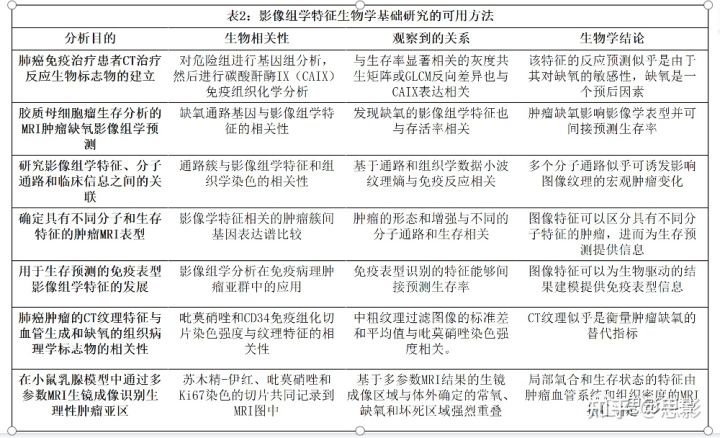

表2给出了旨在为影像组学特征提供生物学见解的不同方法的示例,以及这些发现及其意义。